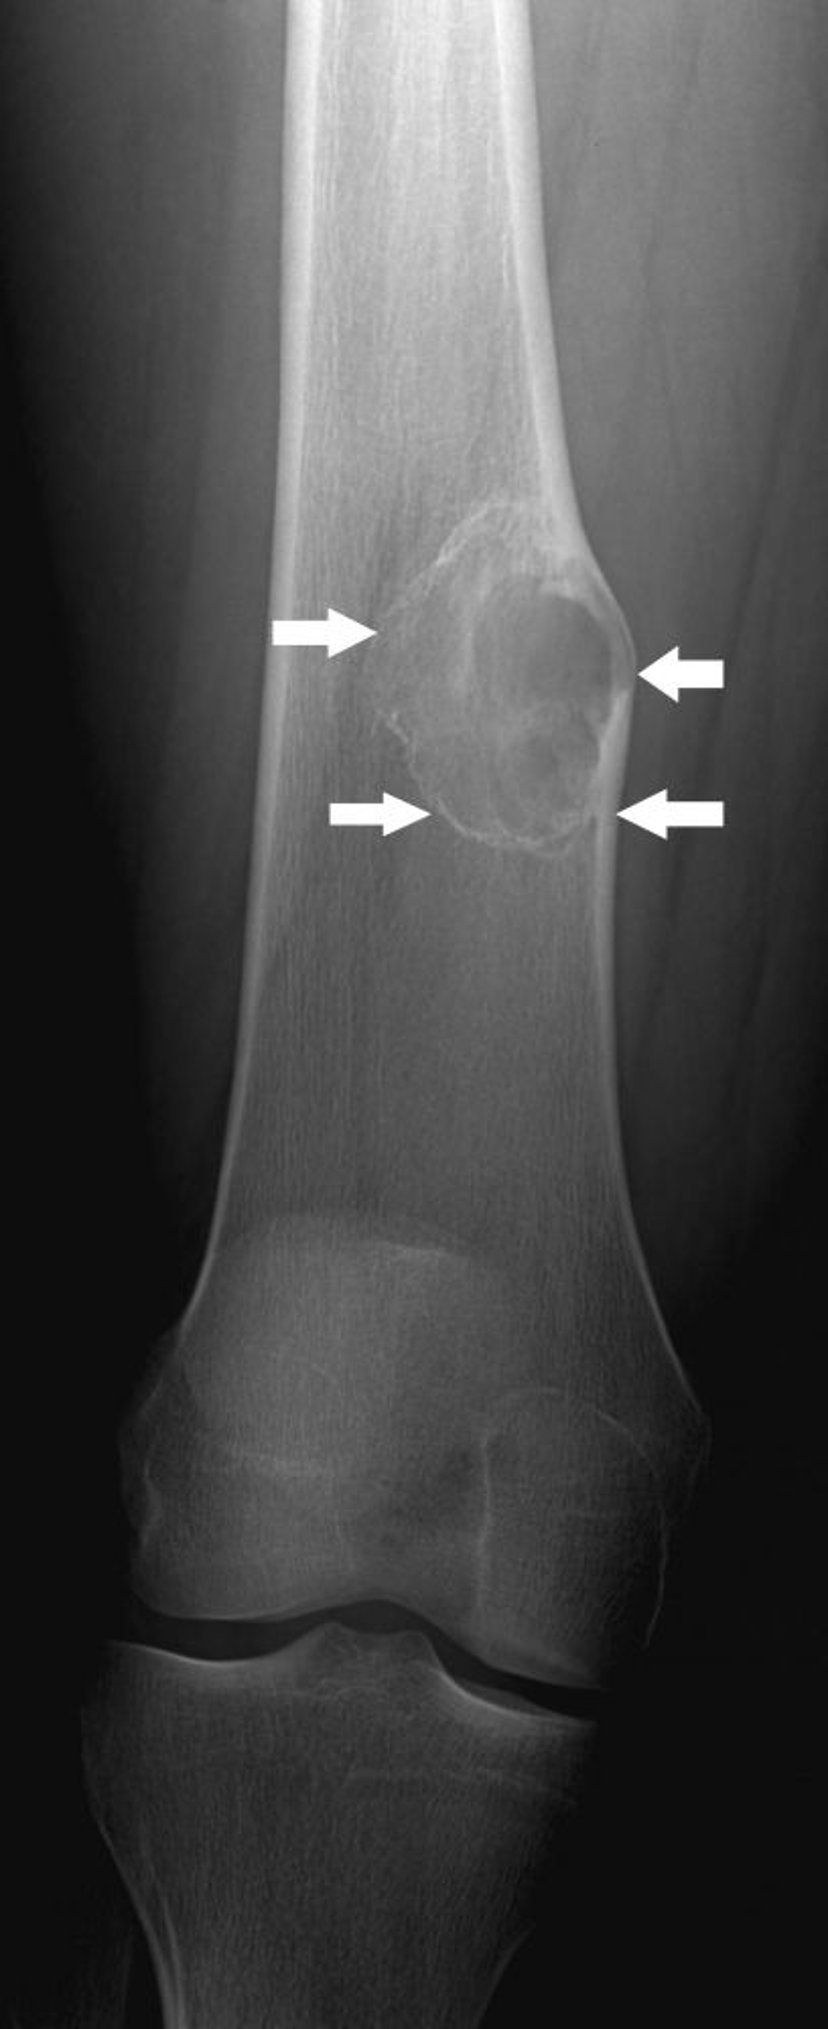

Cette radiographie montre un fibrome non ossifiant (flèches) au-dessus du genou, au niveau de l’os de la cuisse.

Image publiée avec l’aimable autorisation des Drs Michael J. Joyce et Hakan Ilaslan.